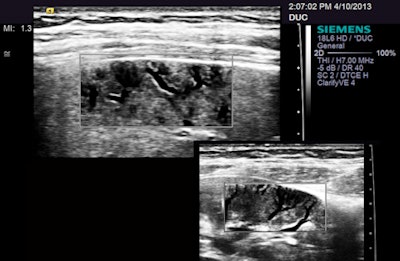

I was really intrigued by one new feature on the S3000 that was billed as a way of cleaning up images. Called Clarify, this seems to be a form of power Doppler that displays flow as black, subtracting intravascular movement from the image -- a kind of blacklight viewing. In any case, this has potential for exposing small peripheral vessels without the color blooming that often wipes out detail in energy and power Doppler usage, especially when filters are set for maximal sensitivity.

A grayscale composite of two images with the same probe but different magnifications, showing small peripheral vessels in the spleen and kidney.I thought both systems would do a good job, but, in truth, I wasn't blown away by either. I made multiple requests for a quote from Siemens but never received one. I was on the verge of investigating refurbished equipment options when I received a note from a new administrator for the outpatient clinics. They had actually gone ahead and purchased basic units from Ultrasonix Medical (now owned by Analogic) for two OB practice participants, having decided there was no need for further advice, other equipment, or apparently for any personnel experienced in clinical ultrasound to operate that equipment.